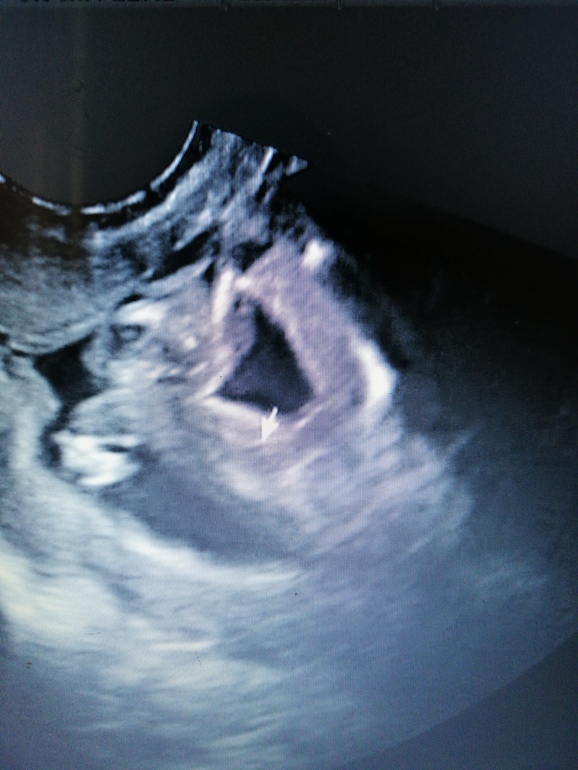

Была сегодня на внеплановом узи(фото)

Поздравляю с доченькой))) Это прекрасно🤗🤗🤗🤗🤗

Поздравляю с принцессой!!😍 Здоровья вам и малышке!